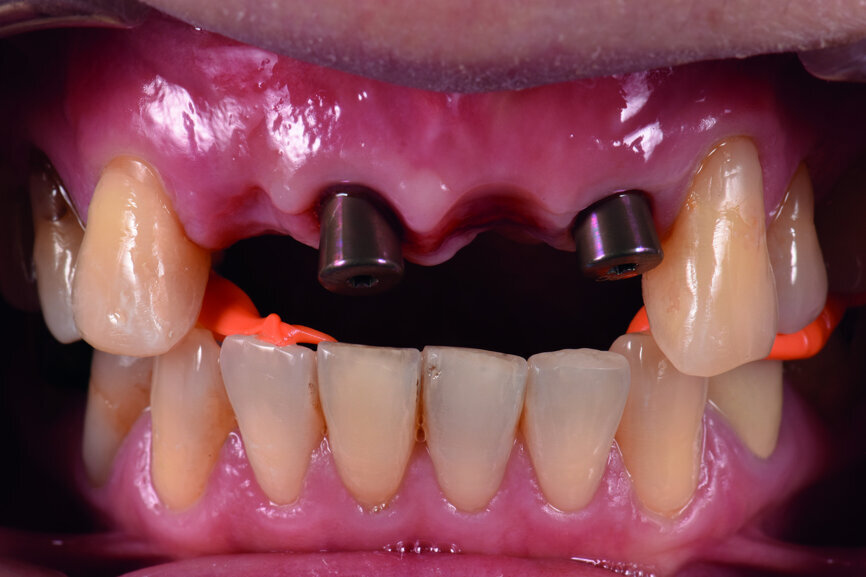

Teeth #12, 21 and 22 were extracted. Tooth #11 underwent early implantation and tooth #22 immediate implantation with GBR (Figs. 5 & 6). After three months of healing, osseointegration had taken place. An implant level impression was taken for fabricating a provisional bridge supported by temporary abutments for teeth #12–22. The technician modified the shape of the artificial gingiva on the model in order to form the proper gingival curve and emergence profile, then finished the provisional bridge, while the dentist modified the gingival shape using an olive-shaped bur intraorally (Figs. 7–18).

Fig. 12: Two impression copings connected for the implant level impression.

Fig. 15: Insertion of provisional abutments.